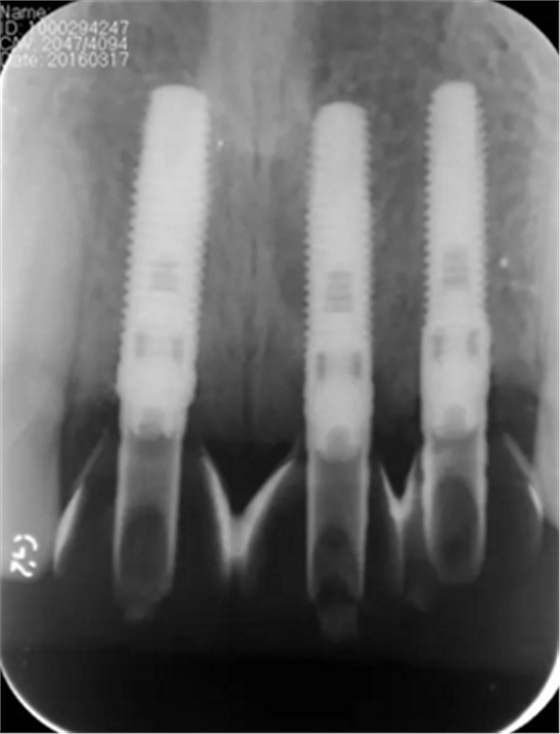

图13 术后即刻根尖片

图24 最终修复后即刻根尖片

(2)即刻种植、即刻临时修复。术中不翻瓣微创拔除牙根,牙槽 窝骨壁完整。在多级导板辅助下完成种植窝洞制备,植入Bego柱形种植 体,型号分别为:上颌右侧中切牙位点4.1mm×15mm、上颌左侧中切牙 位点?3.75mm×15mm、上颌左侧侧切牙位点3.25mm×15mm,扭矩均为 35N·cm。种植体与唇侧骨壁间隙约2mm,植入Bio-Oss®Collagen骨胶 原。戴入桥用钛临时基台,临时冠就位顺利,自凝树脂口内粘接后适当修整 外形,充分磨光,调 至正中 、前伸 和侧方 与对颌牙均无接触。术后 根尖片显示种植体位置、方向良好。

(5)复查。种植体周围骨水平稳定,龈乳头及龈高点位置稳定,龈缘 曲线形态理想,唇侧软硬轮廓良好,功能满意,修复效果符合预期。